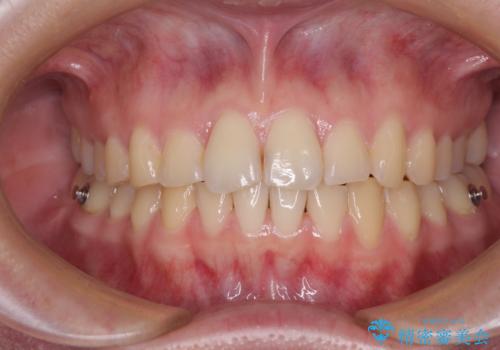

- 食いしばりが気になっていたとのことで来院された患者様です。

当初は睡眠時のマウスピースのみの製作をご希望でしたが、矯正治療の提案をしたところ、インビザラインにて矯正治療を行うこととなりました。

矯正治療中に食いしばりがより強くなることがあるため、半年に1回のペースでボツリヌストキシンによる咬合力緩和を並行して行うこととしました。

咬合力の緩和と食いしばりがちな咬み合わせが改善され、顎の負担が大幅に軽減されました。